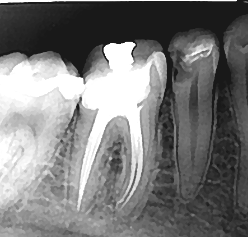

Lečenje zuba predstavlja skup terapijskih mera kojima se tretira unutrašnjost zuba, odnosno mesto gde se nalazi zubna pulpa (zubni živac). Zavisno od stanja zubne pulpe, odnosno da li su u zubni kanal dospeli mikroorganizmi ili ne, lečenje zuba se može obaviti u jednoj ili više seansi. Upotrebom opreme za digitalno određivanje radne dužine i mašinsku obradu kanala korena skrajućuje se vreme postupka i komplikacije nakon intervencije svode na minimum.

Zubni kanal neophodno je obraditi dezinfikovati i trodimenzionalno hermetički zatvoriti. Tako se sprečava prodor bakterija iz usne duplje preko zubnog kanala do koštanog tkiva vilica.